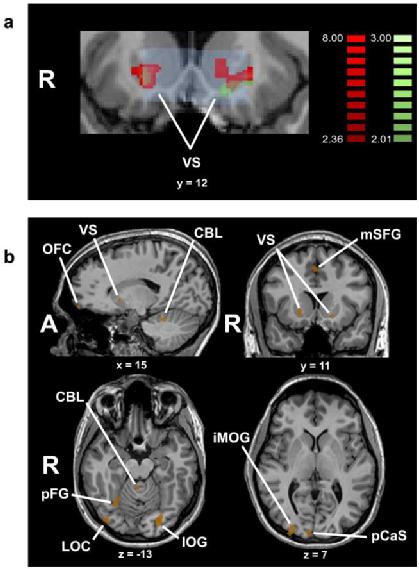

利用最新的脑科学技术,科学家取得了许多发现。例如,在欣赏视觉艺术的时候,大脑不光是视觉区高度活跃,额叶皮层也会激活[5]。而额叶皮层就是大脑里负责复杂的抽象思维和情感活动的脑区。这时候,负责愉悦体验的犒赏通路也会激活,让人产生一种愉悦的感觉[6]。

参与者判断一幅图片是否令人愉悦,结果视觉区、额叶皮层等脑区出现激活脑科学家进一步研究什么样的艺术能引发人审美的体验,总结了很多原则,例如,突出、孤立的物体对大脑的刺激更强烈,还有啊,同类事物组合成一组,就比胡乱摆放的刺激更强。还有啊,大脑对视觉信息有偏好,线条太少,颜色太简单,感觉不刺激;线条太多,颜色太丰富,又感觉受不了。刺激的复杂程度不多不少的时候,大脑最喜欢。[7]